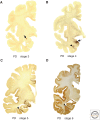

Experimental data indicate that transneuronal propagation of abnormal protein aggregates in neurodegenerative proteinopathies, such as sporadic Alzheimer's disease (AD) and Parkinson's disease (PD), is capable of a self-propagating process that leads to a progression of neurodegeneration and accumulation of prion-like particles. The mechanisms by which misfolded tau and α-synuclein possibly spread from one involved nerve cell to the next in the neuronal chain to induce abnormal aggregation are still unknown. Based on findings from studies of human autopsy cases, we review potential pathways and mechanisms related to axonal and transneuronal dissemination of tau (sporadic AD) and α-synuclein (sporadic PD) aggregates between anatomically interconnected regions.